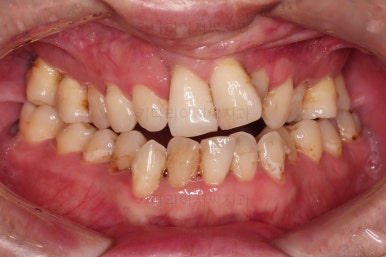

7. 전후 비교사진

치열이 정렬이 잘 되었고요.

웃을 때 보이는 치열의 느낌, 얼굴과의 조화 등 모든 부분이 좋아졌습니다.

부산구순구개열교정 종료 시의 입안의 모습입니다.

위아랫니 정렬이 잘 되었고, 치아 갯수가 위아래가 다르지만 교합도 나쁘지 않게 마무리가 되었습니다.

대문니 2개가 예후가 안좋긴 하나 양옆 치아들과 유지철사로 부착해 두어 최대한 오래 조심히 써보기로 했습니다.